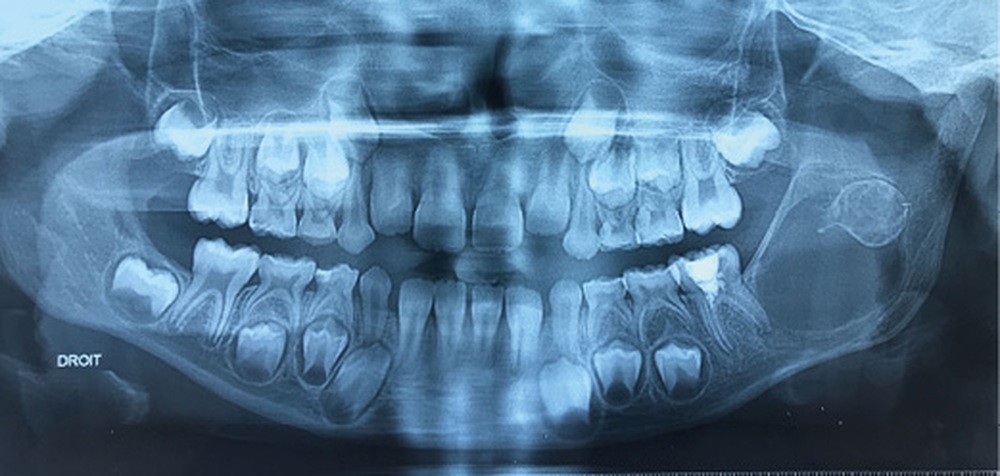

Les kystes et tumeurs bénignes osseuses maxillaires ou mandibulaires chez l’enfant sont le plus souvent asymptomatiques. Ces lésions osseuses sont découvertes de façon fortuite lors d’un bilan radiographique de routine réalisé par l’odontologiste pédiatrique ou l’orthodontiste [1-3]. Néanmoins, des lésions peuvent parfois se développer rapidement et être destructrices [1, 2]. Certains signes cliniques spécifiques à la chronologie de l’éruption dentaire chez l’enfant doivent nous alerter tels qu’un retard d’éruption dentaire ou une éruption dentaire asymétrique (fig. 1). D’autres manifestations cliniques, moins spécifiques à l’enfant, peuvent également orienter le clinicien sur la présence d’une pathologie osseuse sous-jacente : mobilité dentaire, douleur, tuméfaction, limitation de l’ouverture buccale, trouble neurosensoriel, etc. [3]. C’est la radiographie panoramique qui va ensuite mettre en évidence/confirmer la présence d’une lésion intra-osseuse (fig. 2).